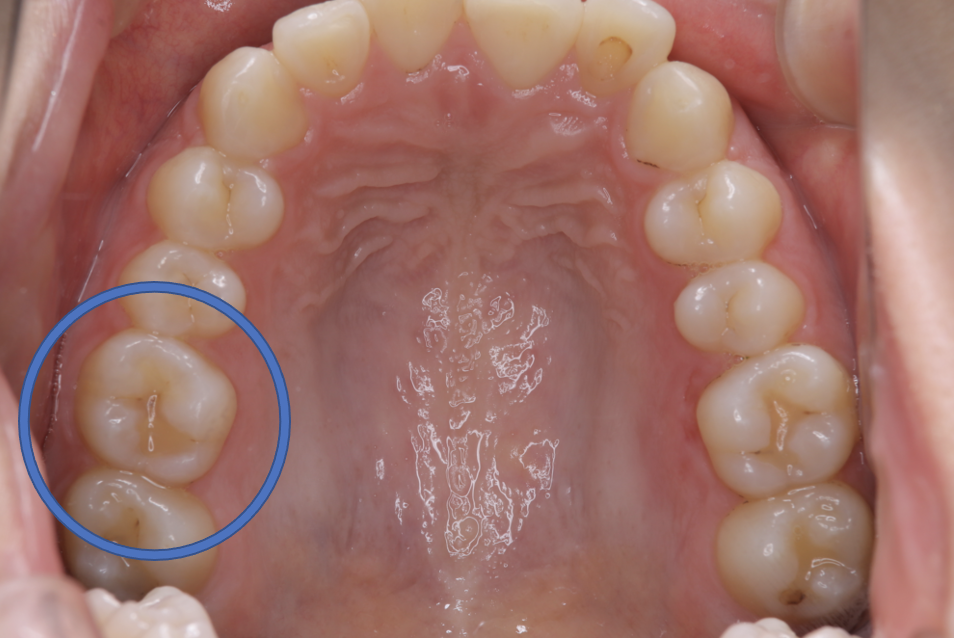

Before

| 備考 | 院長より プラスティック修復部の内部に虫歯が進行してしまっていたケースです。中を開けて見てみると、外から想像するよりもはるかに虫歯が 広がってしまっていました。幸運にも神経を保存できたので、生きた臓器としてまだ使うことが可能です。今回は部分的な詰め物で対応することができたケースです。 |